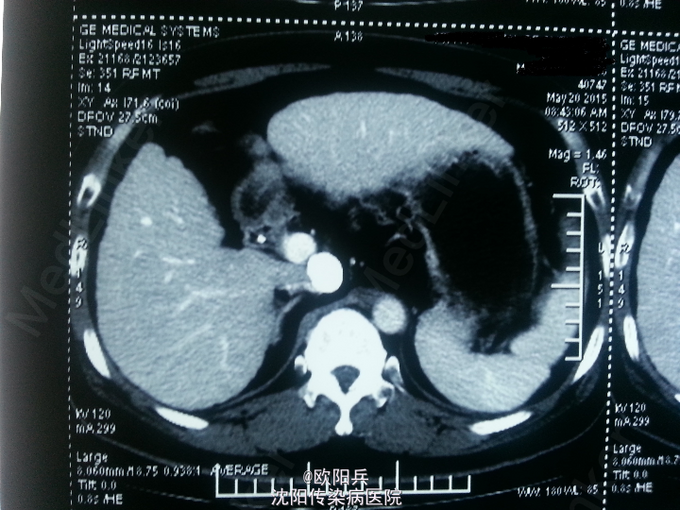

查体:神清语明,面色晦暗,巩膜无黄染,浅表淋巴结无肿大,心肺听诊无异常,腹软,无压痛,肝脾肋下未触及,移动性浊音阴性,肠鸣音正常,双下肢无水肿,扑翼样震颤阴性。 化验:血细胞分析(五分类):*白细胞计数 3.6 10^9/L、*血小板计数 113.0 10^9/L↓、*血红蛋白 166 g/L、中性粒细胞百分比 60.7 %,肝功酶谱:*丙氨酸氨基转移酶 92 U/L↑、*总蛋白 75.0 g/L、*白蛋白 47.0 g/L、*总胆红素 24.0 umol/L↑,糖化血红蛋白检测:糖化血红蛋白 13.50 %↑,*葡萄糖测定:*葡萄糖 15.66 mmol/L↑,血清离子测定:*钾 4.61 mmol/L,肾功能检测:*尿素 5.25 mmol/L、*肌酐 47.3 umol/L↓,血浆氨测定:血氨 29.00 ,凝血五项:凝血酶原时间 9.5 秒↓,乙肝六项:乙型肝炎病毒表面抗原 阳性(+) ↑、乙型肝炎病毒e抗体 阳性(+) ↑、乙型肝炎病毒核心抗体 阳性(+) ↑,丙型肝炎抗体测定(发光法):丙肝抗体 0.01 S/CO,甲胎蛋白测定:甲胎蛋白 7.29 ng/mL。 心电图:正常。 彩超(2015-5-17我院门诊):肝硬化、脾面积大,肝右叶高回声性质待定。 CT:1、肝尾叶占位介入术后改变;2、脾大,肝硬化,肝内多发RN可能性大。

根据患者病史、临床表现及目前辅助检查分析诊断:1、乙肝肝硬化 代偿期 活动性(C-P A级);2、原发性肝癌(肝尾叶)介入术后;3、2型糖尿病。主要诊断依据有: 1、患者乙肝肝硬化、肝癌介入病史明确,2型糖尿病史2年余。2、查体:面色晦暗,移动性浊音(-)。3、化验:患者肝功示转氨酶升高,无低白蛋白血症,C-P评分5分,支持乙肝肝硬化 代偿期 活动性(C-P A级)。糖化血红蛋白 13.50 %↑,葡萄糖 15.66 mmol/L↑,支持2型糖尿病。关于鉴别诊断,患者无酗酒史,不考虑酒精性肝病。其肝癌经DSA下肝动脉造影证实,无需鉴别。患者复查增强CT示肝尾页栓塞密实,边缘无强化,可暂无进一步处理,定期复查。本次住院行常规护肝抗肿瘤治疗。

患者半年前行介入治疗,效果如图,此类患者需密切观察肿瘤进展,目前暂无特殊处理。